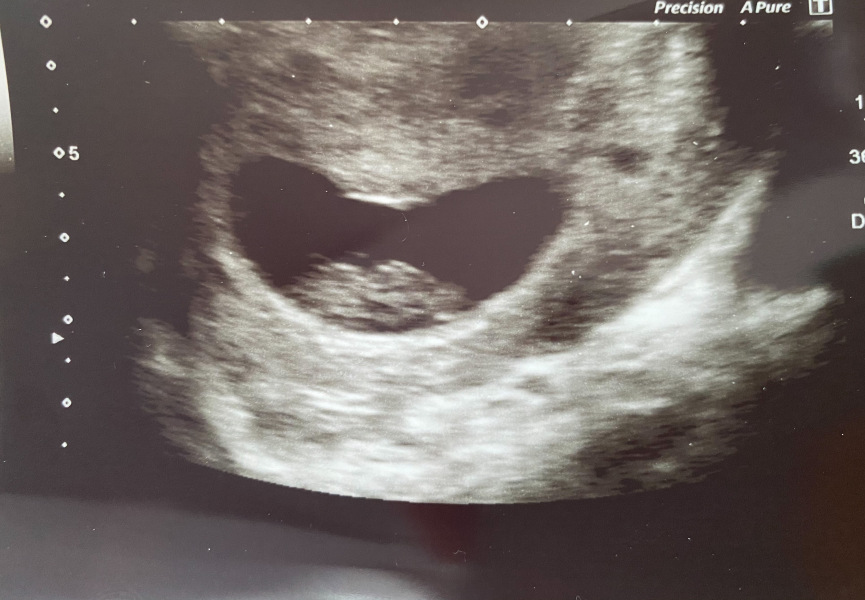

So so happy to say everything is looking great! We saw the little bean with a really strong heartbeat. Measuring my 8+1 dates exactly which is very reassuring. Baby is about 16mm. Got a wee scan pic too and I can’t believe how much they’ve grown since my scan 10 days ago! You can see little limb nubs and everything 🄹

@purplecolouroffunk such wonderful news and what an amazing picture! So happy for you Purple šŸ’œ xxx

jellyfish2 · 21/07/2024 17:56

@purplecolouroffunk amazing! I'm so happy all was well 🄰 what a great picture too šŸ˜

That’s such a beautiful picture @purplecolouroffunk 🄰

That's a beautiful picture @purplecolouroffunk I'm so glad for you.